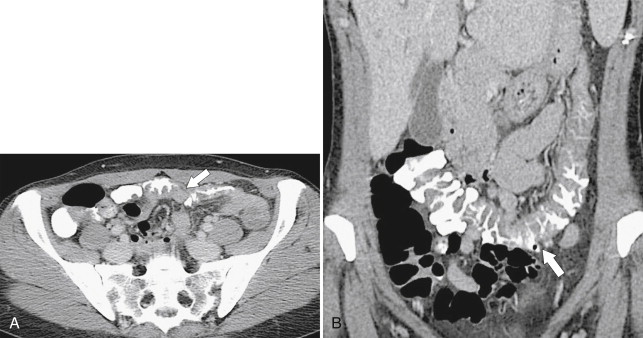

Often the infectious etiology cannot be determined by imaging alone because all the agents cause nonspecific colonic wall thickening and some cause a pancolitis, including Escherichia coli (although this colitis can be severe [ Fig. 5-47 ]) and those involved in traveler’s diarrhea ( Fig. 5-48 ). Other pathogens tend to affect specific colonic areas more than others. Campylobacter sp. is sometimes indistinguishable from UC ( Fig. 5-49 ), but is often confined to the rectum. Other rectal colitides include gonococcal and herpes colitis. Shigella sp. primarily affects the left side of the colon, whereas Salmonella typhi, tuberculosis, Yersinia, and amebiasis are focally confined to the ileocecal region with or without local adenopathy.

Strongyloides infection can mimic UC in its diffuse form but can also present with focal right colonic disease ( Fig. 5-50 ). Actinomyces infection is usually secondary to pelvic colonization of intrauterine contraceptive devices and may cause a focal, either cecal or rectosigmoid, colitis ( Fig. 5-51 ). Actinomyces may also be associated with right-sided ileocecal infection after secondary infection following appendectomy.

Figure 5-51, BE ( A ) and axial contrast-enhanced CT ( B ) in a 39-year-old woman with pelvic actinomycetes infection with sigmoid wall thickening ( arrow ) and narrowing ( small arrows ) and a pelvic abscess ( arrowhead ).